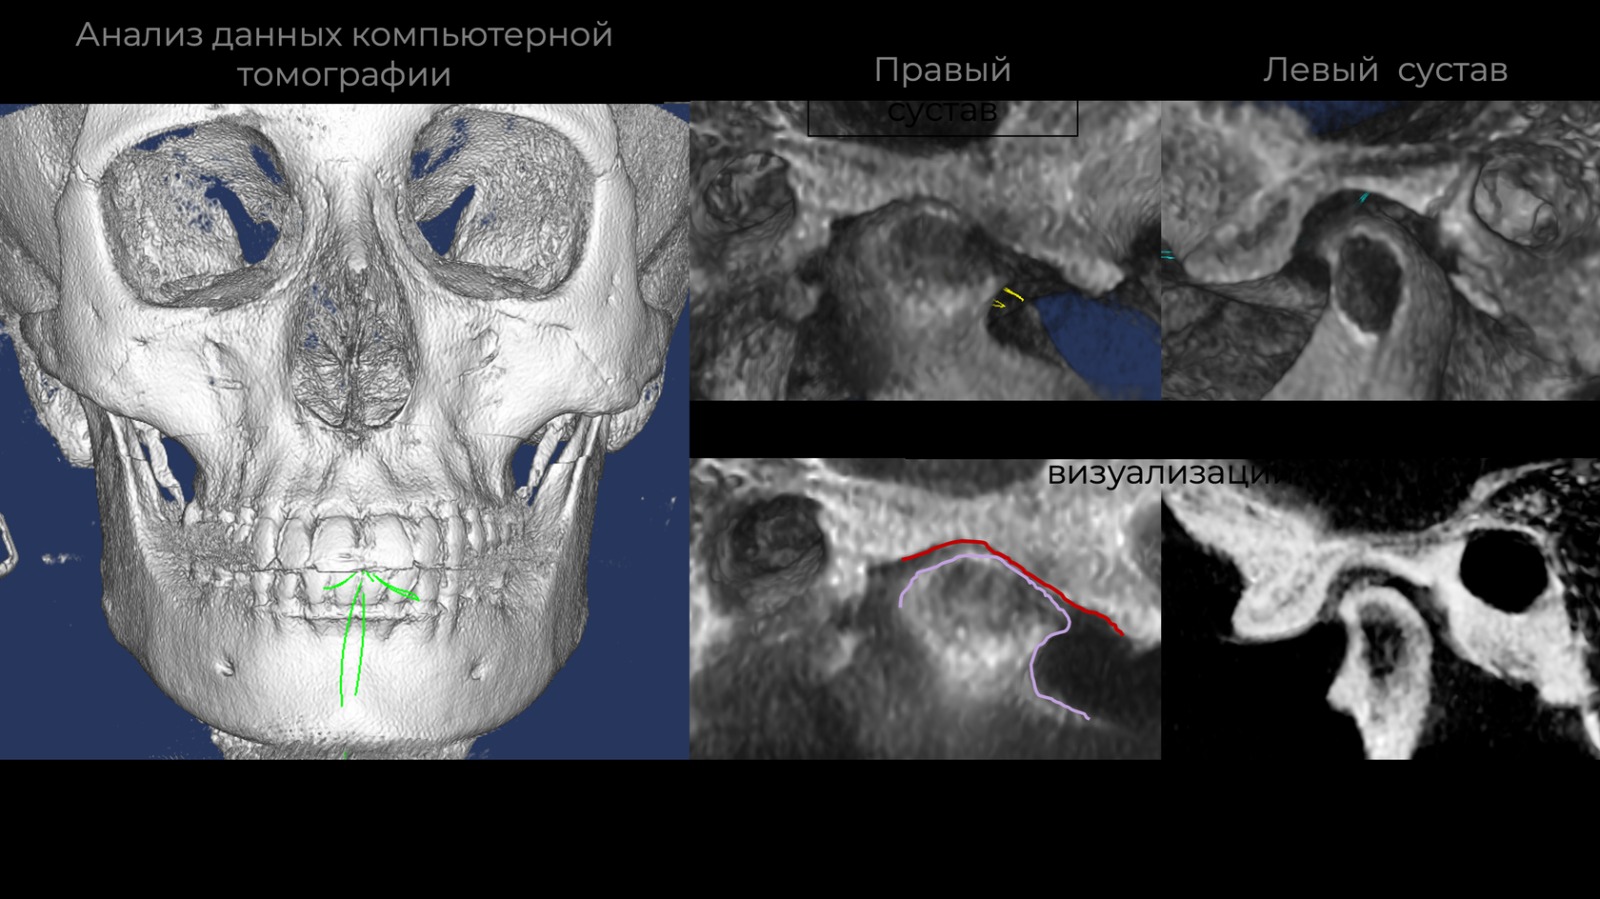

Возможности цифровой функциональной диагностики.

Для каких пациентов необходимо использовать полный цифровой протокол с данными КТ, МРТ, индивидуальной модели аксиографии.

Фотографии учебного материала